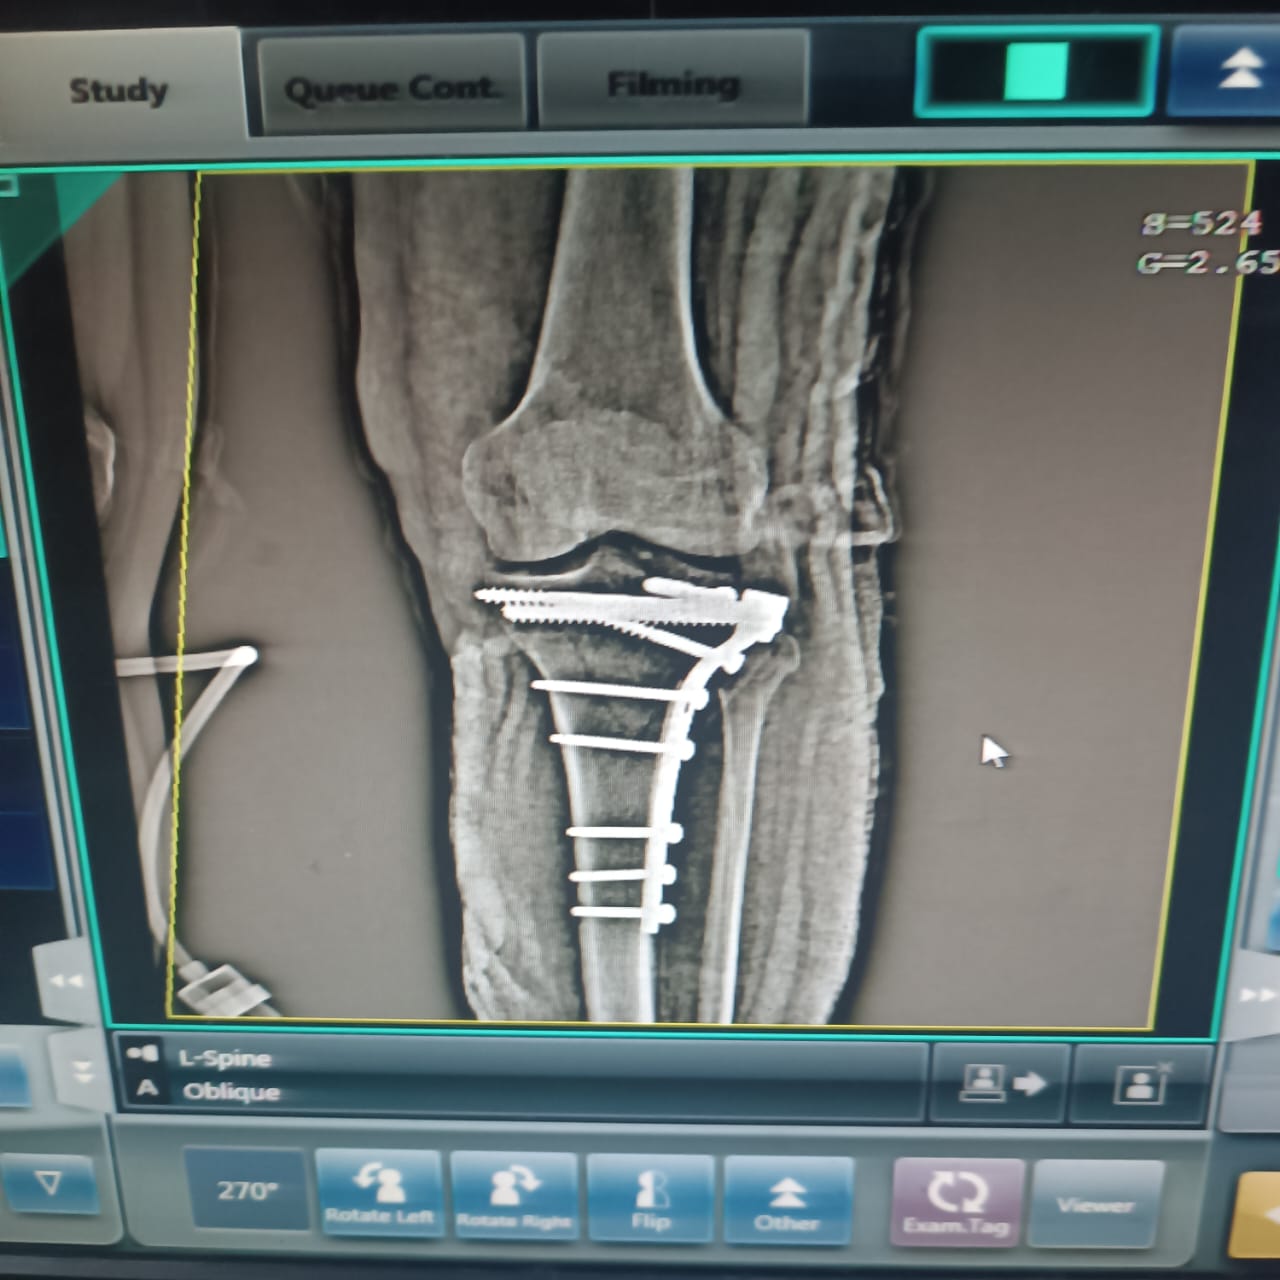

هل يوجد فرق بين صورتي الأشعة؟

كنت عاوز اعرف من دكتور عظام وأشعة في فرق بين الصورتين دي الاشعه قديمه وجديده مع بعض.

دي صورتين القديمه والجديده